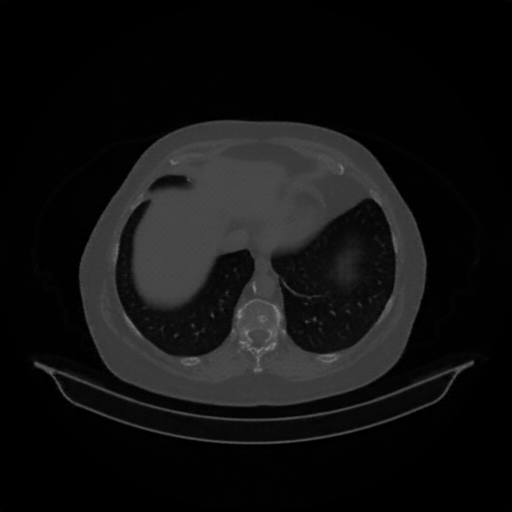

Image Grid

4Γ—3 grid: Rows show different image types (Original NATIVE, Reconstructed NATIVE, Original VENOUS, Generated VENOUS), Columns show windowing techniques (No Window, Lung Window, Mediastinum Window)

Original NATIVE CT scan (input)

No window - Raw intensity values

Reconstructed NATIVE CT scan (cycle consistency)

Original VENOUS CT scan

Generated VENOUS CT scan (A→B translation)